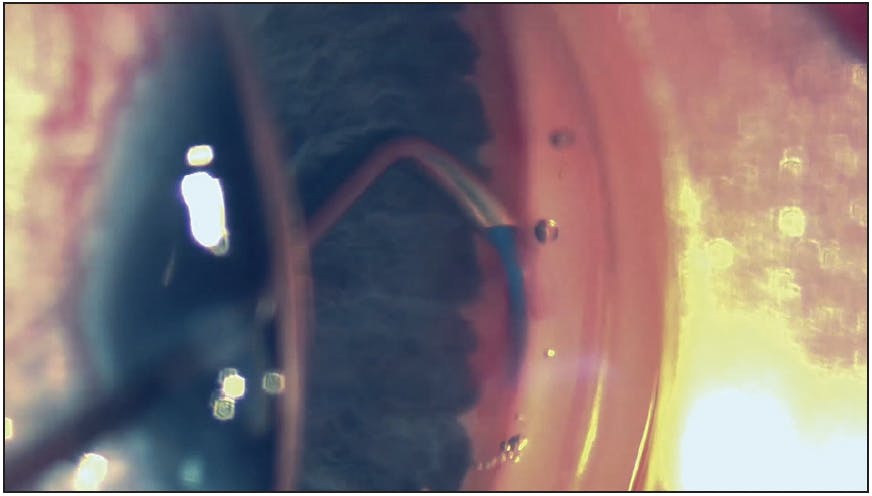

The patient was very keen about a minimally invasive surgical option and wanted to have the same quick return to daily activities that he experienced after surgery in 2018. A standalone pseudophakic OMNI procedure was planned. During surgery, a 360º viscocanaloplasty without trabeculotomy was successfully performed. The microcatheter was inserted (Figure) between two trabecular bypass stents and slid behind them smoothly with no feeling of obstruction and minimal stent movement. The microcatheter was able to pass through Schlemm’s canal both left and right. The trabecular stents were left in situ because they were believed to be functioning as suggested by the initial IOP reduction in 2018. It was suspected, however, that they may not be fully in canal.